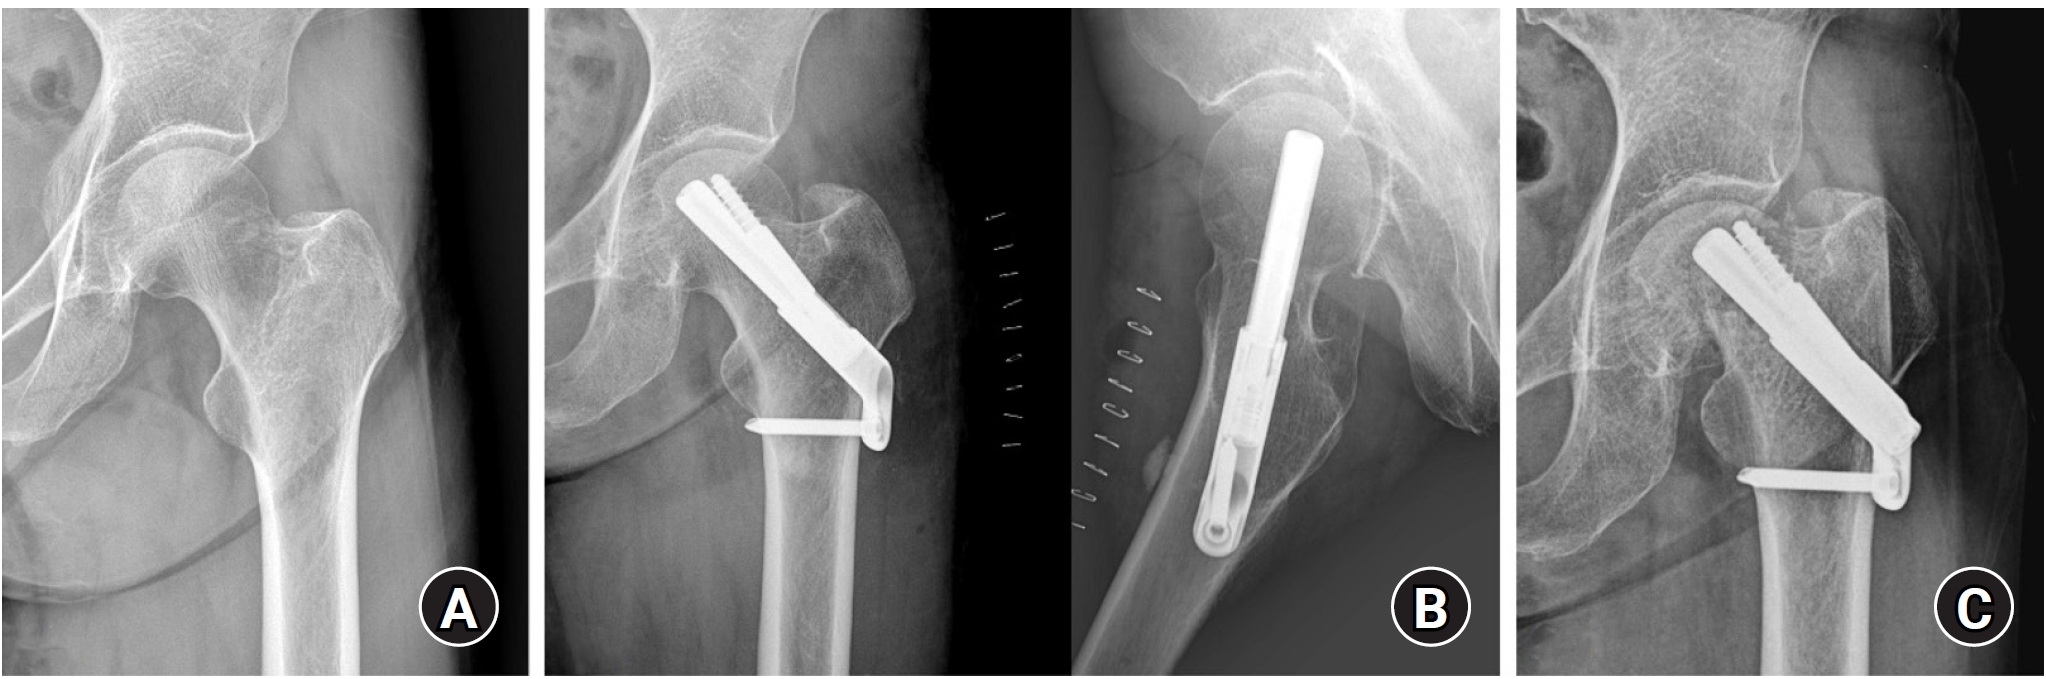

Standardized anteroposterior and lateral radiographs of the hip were obtained immediately postoperation and at each follow-up visit (6 weeks, 3 months, 6 months, 1 year, and annually thereafter). Radiological union was defined as the disappearance of the fracture line, accompanied by the absence of pain on full weight-bearing. Femoral neck shortening was calculated as the difference in the distance from the center of the femoral head to the lateral cortex of the femur between the immediate postoperative and final follow-up radiographs (Fig. 2). Femoral neck shortening was measured independently by two experienced orthopedic surgeons, and the average of their values was used for the analysis. Complications, including fixation failure (e.g., screw cut-out or excessive sliding), AVN of the femoral head, nonunion, and the need for revision surgery, were investigated.

Radiological outcomes

At the final follow-up, the union rate was 87.5% (21/24) in the FNS group and 95.8% (23/24) in the DHS group, with no statistically significant difference between the two groups (P=0.296) (Figs. 2, 3). The mean femoral neck shortening was measured at 6.1 mm in the FNS group and 5.9 mm in the DHS group, and no significant difference was observed (P=0.427).

Fig. 2.

(A, B) A 67-year-old female patient with a right femoral neck fracture (Garden type 1) treated with the femoral neck system. (C) The postoperative 4-year radiograph shows a well-healed fracture site and no complications related to the implant. Femoral neck shortening (D2‒D1) was calculated as the difference in the distance from the center of the femoral head to the lateral cortex of the femur between the immediate postoperative and final follow-up radiographs.

Fig. 2. (A, B) A 67-year-old female patient with a right femoral neck fracture (Garden type 1) treated with the femoral neck system. (C) The postoperative 4-year radiograph shows a well-healed fracture site and no complications related to the implant. Femoral neck shortening (D2‒D1) was calculated as the difference in the distance from the center of the femoral head to the lateral cortex of the femur between the immediate postoperative and final follow-up radiographs.